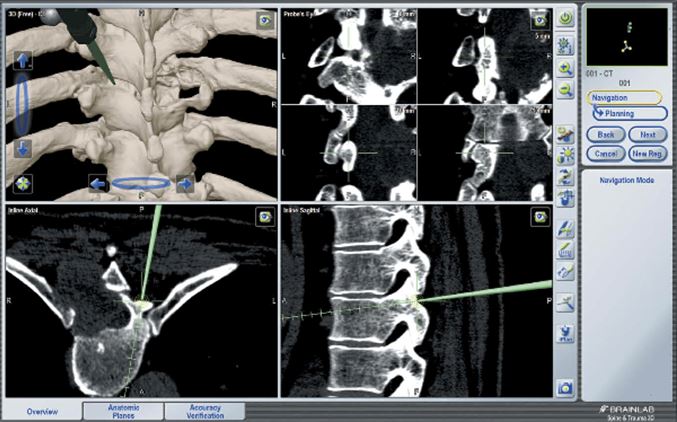

Como con las técnicas mínimamente invasivas hacemos unas heridas de menor tamaño en la piel nuestra capacidad para ver las distintas estructuras de la columna vertebral es menor por lo que necesitamos de técnicas auxiliares que nos ayuden a ver las zonas de la columna y poder trabajar con seguridad.

Estas técnicas auxiliares pueden ser el empleo de un escáner que mediante programas informáticos realizan una reconstrucción tridimensional de la columna (navegación vertebral), también se pueden emplear microscopios especiales que aumentan la visión de la zona; uso de tubos dilatadores que se colocan en la piel y nos permiten separar los músculos sin lesionarlos e introducir a través de ellos los instrumentales necesarios para la operación. (Fig 1 y 2)